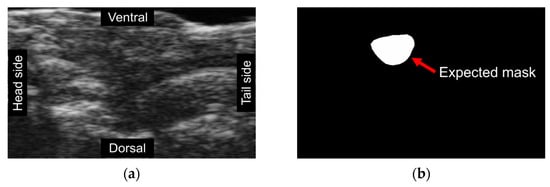

Figure 2.

Unsupervised segmentation trials utilizing different methods failed to detect expected masks. Each image is represented by a distinct color, signifying the model-generated segmentation regions. (a) An original frame, where individuals without training could not accurately classify the ventricle’s location due to the lack of ground truth labels; (b) An expected mask created manually; (c) A result frame obtained using modified CNNs revealing that the model is susceptible to color interference and, as such, is unsuitable for echo-videos; (d) A result of Dino demonstrating the model was incapable of detecting the ventricle due to background noise.

Dino, an implementation of self-supervised learning on Vision Transformers (ViTs) [20], was applied for unsupervised video segmentation(Figure 2d). Dino employs a simplified self-supervised training approach by predicting the output of a teacher network. It comprises a momentum encoder and uses a standard cross-entropy loss. Dino has two key features that distinguish it from CNNs and supervised ViTs: it explicitly encodes semantic information about image segmentation such as scene layout and object boundaries.

However, these methods are not robust enough to handle echo-video’s blurring and signal noise, making them unsuitable for the image segmentation task and ejection fraction assessment. As a result, supervised image segmentation has been the only method to demonstrate sufficient accuracy in this work.